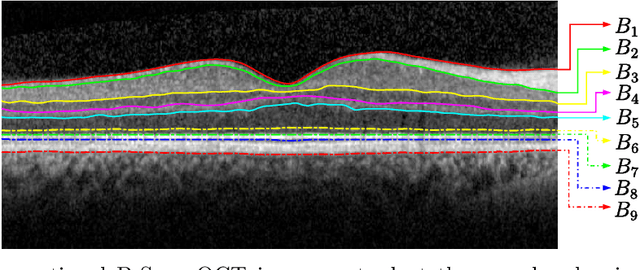

Abstract:In this paper, we propose a novel retinal layer boundary model for segmentation of optical coherence tomography (OCT) images. The retinal layer boundary model consists of 9 open parametric contours representing the 9 retinal layers in OCT images. An intensity-based Mumford-Shah (MS) variational functional is first defined to evolve the retinal layer boundary model to segment the 9 layers simultaneously. By making use of the normals of open parametric contours, we construct equal sized adjacent narrowbands that are divided by each contour. Regional information in each narrowband can thus be integrated into the MS energy functional such that its optimisation is robust against different initialisations. A statistical prior is also imposed on the shape of the segmented parametric contours for the functional. As such, by minimising the MS energy functional the parametric contours can be driven towards the true boundaries of retinal layers, while the similarity of the contours with respect to training OCT shapes is preserved. Experimental results on real OCT images demonstrate that the method is accurate and robust to low quality OCT images with low contrast and high-level speckle noise, and it outperforms the recent geodesic distance based method for segmenting 9 layers of the retina in OCT images.

Abstract:Optical coherence tomography (OCT) is a non-invasive imaging technique that can produce images of the eye at the microscopic level. OCT image segmentation to localise retinal layer boundaries is a fundamental procedure for diagnosing and monitoring the progression of retinal and optical nerve disorders. In this paper, we introduce a novel and accurate geodesic distance method (GDM) for OCT segmentation of both healthy and pathological images in either two- or three-dimensional spaces. The method uses a weighted geodesic distance by an exponential function, taking into account both horizontal and vertical intensity variations. The weighted geodesic distance is efficiently calculated from an Eikonal equation via the fast sweeping method. The segmentation is then realised by solving an ordinary differential equation with the geodesic distance. The results of the GDM are compared with manually segmented retinal layer boundaries/surfaces. Extensive experiments demonstrate that the proposed GDM is robust to complex retinal structures with large curvatures and irregularities and it outperforms the parametric active contour algorithm as well as the graph theoretic based approaches for delineating the retinal layers in both healthy and pathological images.